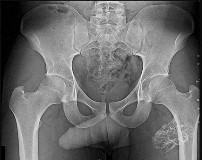

A 35-year-old male sustains an anteroposterior compression (APC) type II pelvic ring injury.

During anterior ring fixation via an ilioinguinal approach, massive hemorrhage is encountered posterior to the superior pubic ramus. Which anomalous anatomical connection represents the classic 'corona mortis'?

The 'corona mortis' (crown of death) refers to a vascular anastomosis between the obturator and external iliac (or inferior epigastric) vascular systems. It is located posterior to the superior pubic ramus at a variable distance (average 5-6 cm) from the symphysis pubis and can cause life-threatening hemorrhage if inadvertently disrupted during anterior pelvic ring surgery (ilioinguinal or Stoppa approaches).